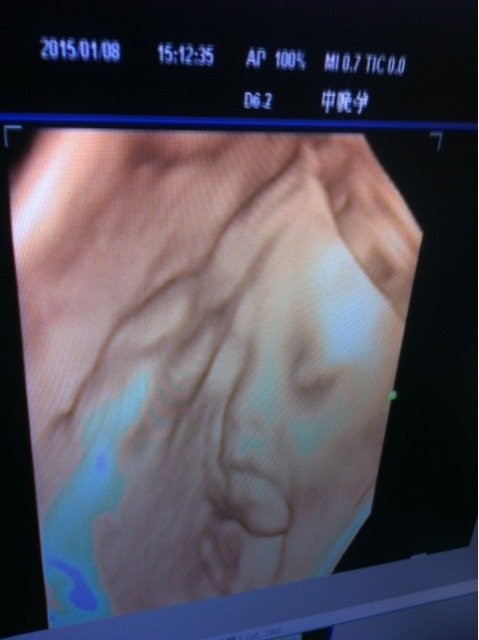

孩子不出生,总是担心来担心去!都快有忧虑症了!今天四维彩超回来,大家帮忙看看宝宝长的有没有缺陷

你好,你发的是胎儿面部四维超声照片,四维彩超注重看胎儿上唇的连续性,没有异常。